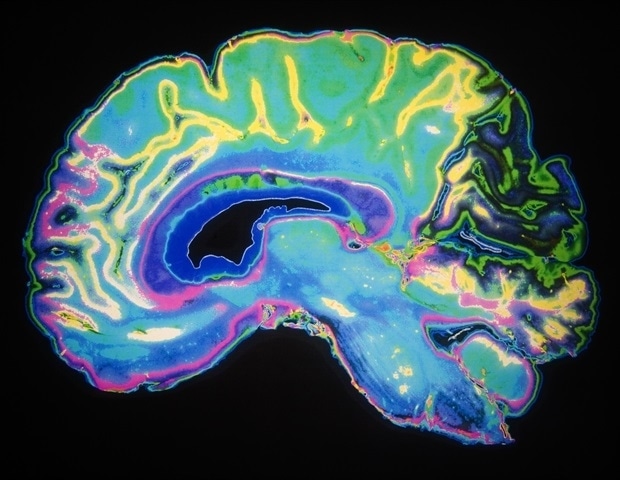

For individuals classified under the poor sleep profile, the study found heightened resting-state connectivity between subcortical brain regions and both sensorimotor and attention networks. Such findings could pave the way for personalized treatment strategies in clinical settings.

The study also highlights the neuroimaging results associated with the different sleep profiles. These unique brain function patterns suggest that individual sleep experiences are intricately linked to both behavioral and cognitive outcomes, influencing not just health but also the brain’s wiring and activity.